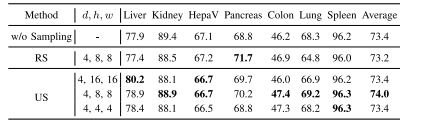

TABLE VIIPERFORMANCE OF VARIANTS OF CADS WITHOUT SAMPLING, WITHRANDOM SAMPLING (RS), OR WITH UNIFORM SAMPLING (US) ONSEVEN DATASETS. THE BEST RESULT IN EACH COLUMN ISHIGHLIGHTED WITH BOLD.d × h × w: PATCH SIZEUSED IN SAMPLING STRATEGIES

表7 无采样、随机采样(RS)及均匀采样(US)三种条件下的CADS变体模型在七个数据集上的性能对比。每列中的最佳结果以粗体突出显示。注:d × h × w 表示各采样策略中使用的补丁块(patch)尺寸。